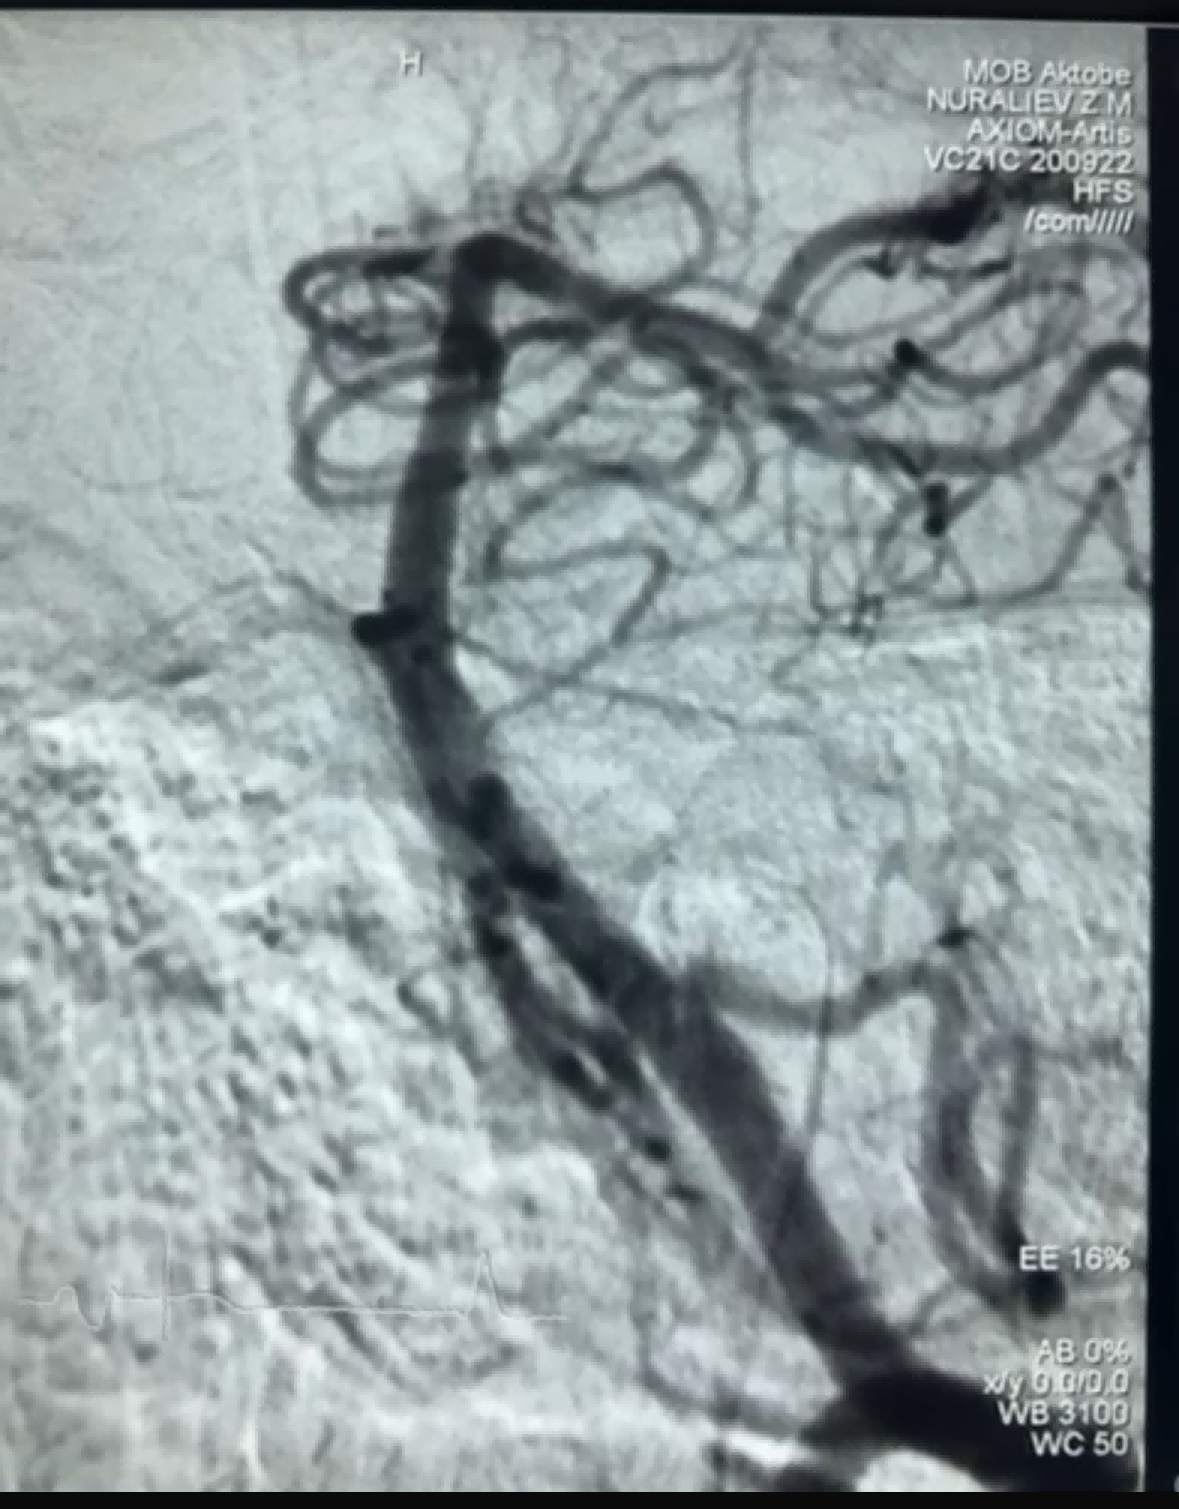

לאחרונה אירע מקרה כריתת פקקת מוצלח בשימוש ב-Dredger Stent Retriever של NeuroSafe Medical Co., Ltd. ל-Dredger Stent Retriever קצה רך לא פולשני, המפחית מאוד את הסיכון לנזק אינטימי, ובעל חור ייחודי בעל צורה מיוחדת עיצוב הלוכד קרישי דם בעיקר על ידי הידוק השינויים בפערים.